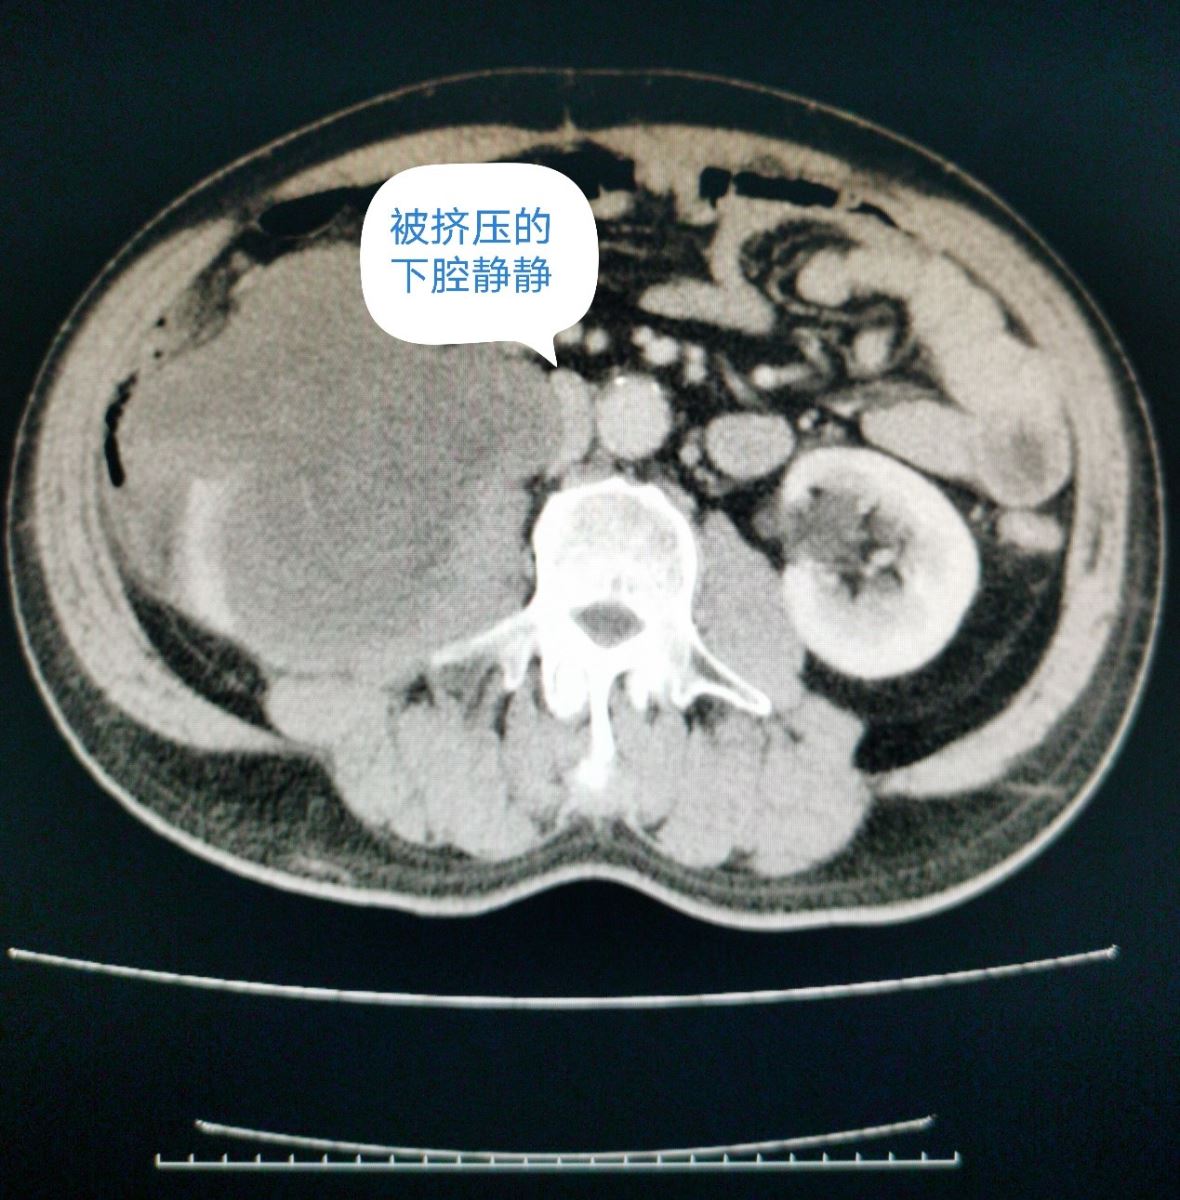

近日,西院肿瘤外科成功为一腹膜后脂肪肉瘤复发患者开展手术。患者于1年半前在外地某三甲医院被诊断为“腹膜后肿物”,行腹膜后肿物切除术,术后病理诊断为“腹膜后脂肪肉瘤”。此后定期复查,1月前,患者自觉左侧腹部可触及包块,伴疼痛,腹胀,食欲下降,消瘦明显。在外院查腹部彩超提示:腹膜后肿物。患者为进一步治疗,来我院。入院后完善检查,进一步明确诊断。全腹增强CT提示:右中腹见团块状混杂密度影,形态不整,右肾变形,内部密度不均,与下腔静脉、胰头、十二指肠,右侧腰大肌关系密切,增强扫描呈混杂密度影。肿瘤外科全体医生对患者病情进行了细致详尽的术前讨论。患者1年半前行腹膜后脂肪肉瘤切除术,此次考虑为腹膜后脂肪肉瘤复发,肿瘤较大,与周围器官关系密切,尤其紧邻下腔静脉,二次手术风险极大,一旦发生下腔静脉意外撕裂,可能造成空气栓塞等致命性危险。全科医生一起反复仔细查阅增强CT,制定详尽的手术计划。并对可能出现的风险及意外进行预判,提出解决方案。与患者家属沟通,详细交待病情,说明治疗方案及手术风险。